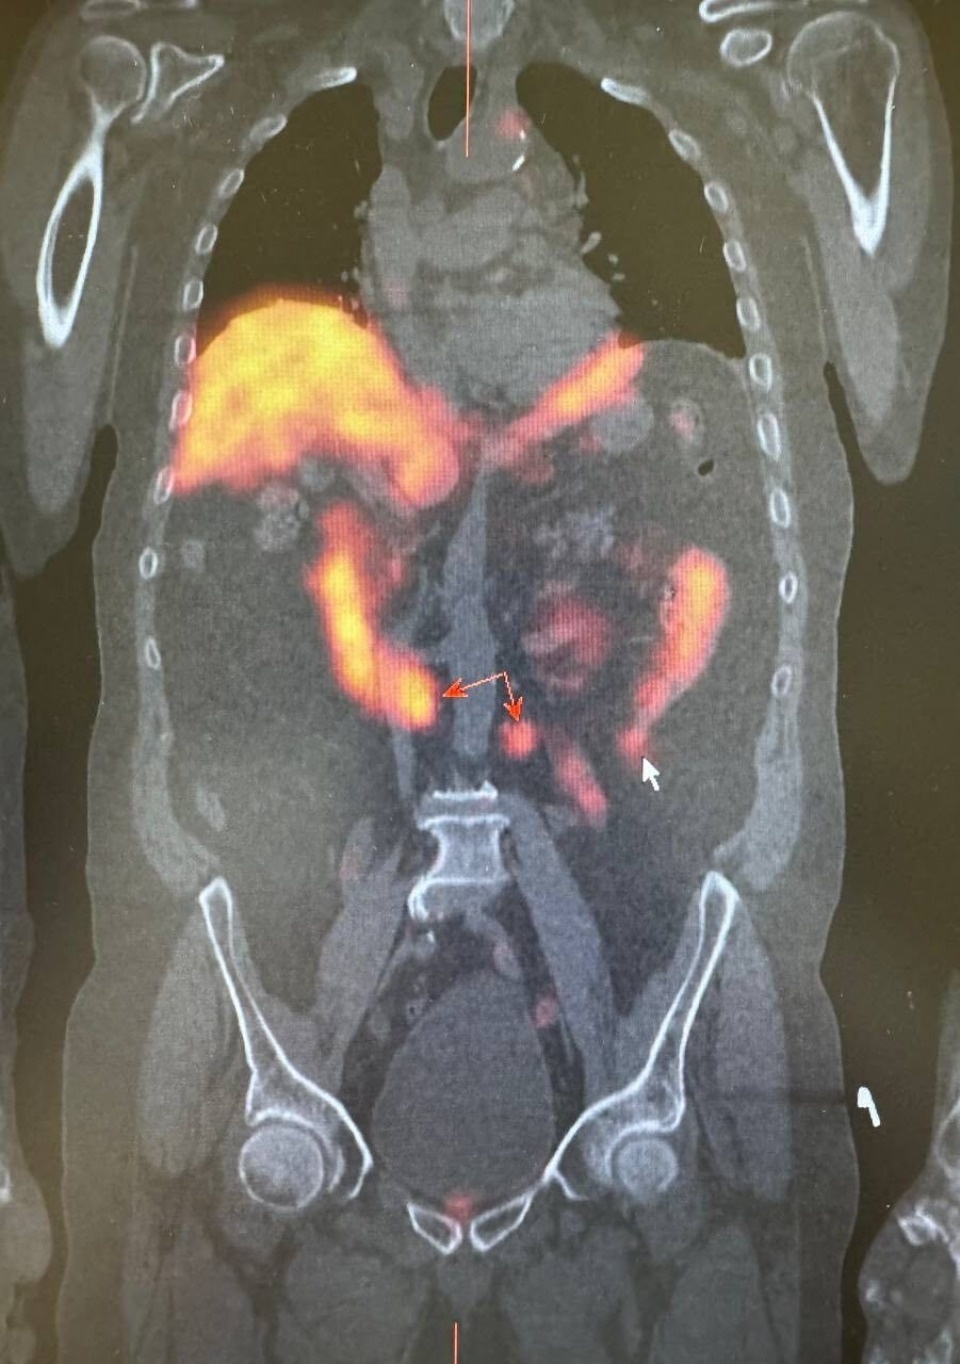

Для получения детальной информации о состоянии лимфатических узлов назначили радионуклидная диагностика. Она позволила определить наличие злокачественного опухолевого процесса в предстательной железе и подтвердить метастатическое поражение ранее выявленных лимфатических узлов к грудной клетке.

Помимо этого, исследование показало активное накопление технеции ПСМА в парааортальных лимфатических узлах с обеих сторон. «При этом, важно отметить, что на компьютерной томографии не было явных структурных изменений, что затрудняло оценку их состояния и возможности метастазирования», – обратили внимание в пресс-службе министерства здравоохранения Псковской области.